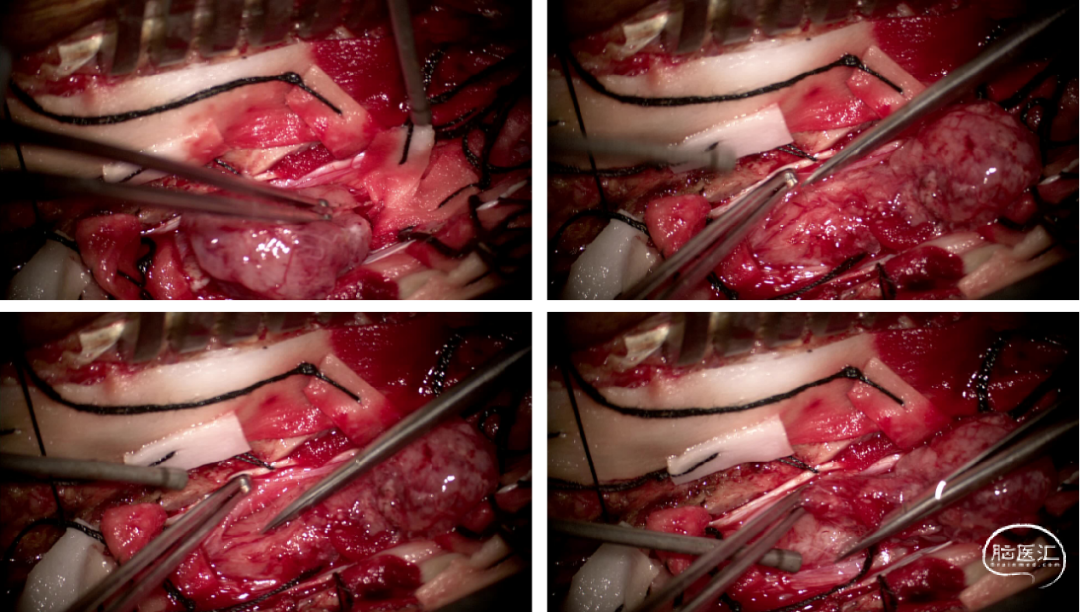

手术情况

硬脊膜张力高,脊髓向背侧膨出,与脊髓腹侧粘连紧密,肿瘤挤压脊髓,肿瘤边界分离,减少对胸髓的牵拉,降低了术后患者神经功能发生的概率,术后患者肢体麻木症状改善。